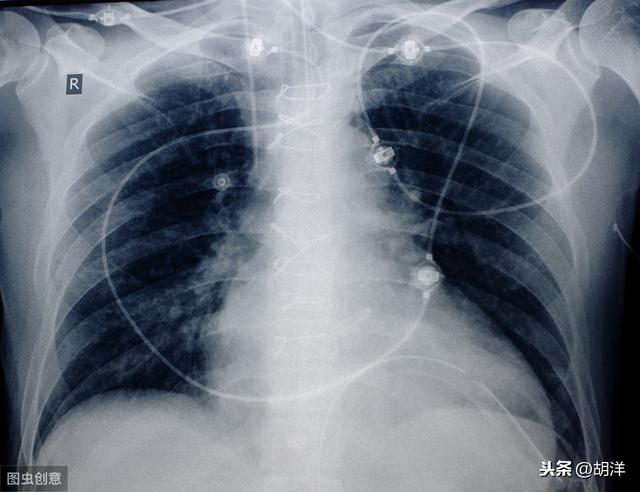

1.呼吸不全は、一般に患者の空気不足として知られ、進行肺癌患者に最も多い。中枢性肺癌では気管や主気管支が閉塞して空気が入りにくくなり、肺の無気肺が大きくなると、次第に息切れや呼吸困難に悩まされるようになる。胸膜転移により大量の胸水が貯留し、肺組織が圧迫されて肺が再開通できなくなる患者もいる。また、肺病変が多すぎて有効呼吸膜面積が著しく減少している患者もいる。これらの理由はすべて、最終的に胸部圧迫感、息切れ、座位呼吸を引き起こし、最終的には呼吸不全に至る。

人間は、肺の空気交換機能に頼って酸素呼吸を行い、地球上で生存している。肺不全は、巨大な腫瘍、大量の胸水、広範な肺転移、気道閉塞などの進行した肺がんによって引き起こされることが多い。

この患者はまだ39歳で、胸のつかえと息切れがあり、右肺の腺がんと診断され、多量の胸水が貯留し、右肺全体の機能が失われていた。このような重篤な状態は高齢者にやや多く、放置すればすぐに呼吸不全に陥る。幸いなことに、彼女は標的治療に感受性があり、胸水をコントロールしながら3年以上腫瘍と共存している。

(1) 呼吸不全で死亡

私たちが呼吸するには両方の肺が必要で、肺が腫瘍でいっぱいになると、呼吸する能力を失い、がんが気道をふさぐこともあり、胸水もたまり、その多量が肺を圧迫して呼吸困難を引き起こす。肺が働けなくなれば、やがて酸素が不足し、全身の臓器が血液と酸素を奪われ、ついには死んでしまう。

1.呼吸不全:周知のように、肺は呼吸器の主要な臓器であり、肺がん患者、特に進行期の肺がん患者は、がん細胞が正常な肺組織を破壊するため、呼吸困難に陥ります。がん細胞が脳転移、肝転移、骨転移など全身に広がれば、全身の体内環境が乱れ、呼吸不全の原因にもなる。進行した肺がん患者の大半は、呼吸不全に陥った時点で末期を迎えている可能性があり、家族は心理的な準備をする必要がある。